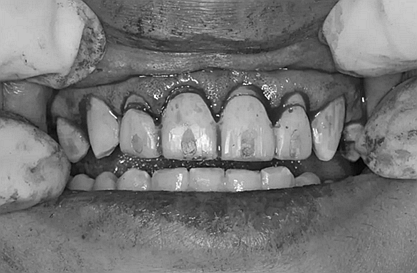

我們的主人今年才25歲,可卻從很小的時候就嗜好喝可樂等碳酸飲料,幾年下來,讓我們兄弟姐妹們整天浸在碳酸里受這蝕骨之痛,原本皎潔的外貌如今早己經(jīng)是腐蝕不堪、丑陋無比,更有甚者,一些兄弟姐妹們已經(jīng)病入膏肓,被病痛折磨奄奄一息。

下面是醫(yī)生眼中和ct下的我們

一身病痛啊

牙結(jié)石、牙齦炎癥、牙體殘缺、慢性牙髓炎、蛀牙......

再來看看曾經(jīng)的我們